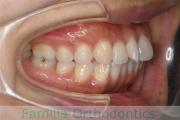

- ≫治療前

上顎

下顎

前歯の関係など

右側

正面

左側